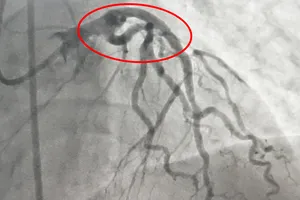

BV công, tư bắt tay cứu anh xe ôm bị nhồi máu cơ tim